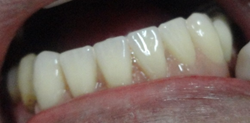

Nesta fotofgrafia vemos ma gengiva normal. A cor é rosa pálida, a textura é semelhante a uma casca de laranja em miniatura, as papilas são finas ocupando o espaço interdentário, terminam bem delgadas na superfície do esmalte. Não sangram na escovação.

Na parte superior destes dentes vemos claramente uma Gengivite instalada. A gengiva fica, vermelha, lisa devido ao edema. As papilas ficam mais vermelhas e aumentam de volume e quando tocadas pelo fio dental sangram com facilidade.